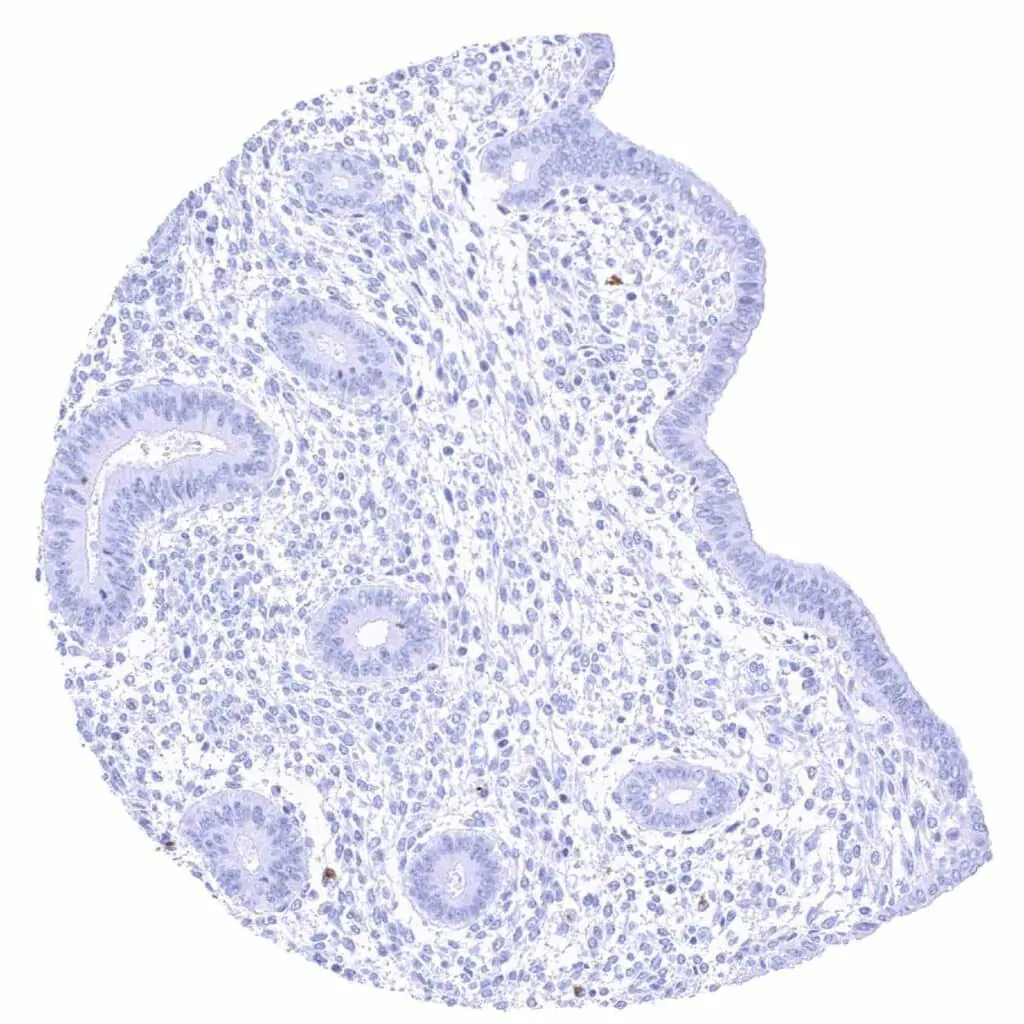

Tonsil, surface epithelium

Tonsil